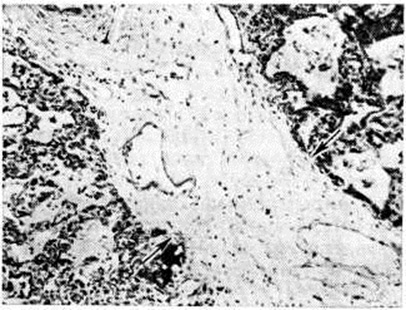

В большей части случаев альтеративный компонент воспаления выражен слабо. Вначале отмечается только полнокровие структурных образований лёгкого, в которых находятся и размножаются бактерии. Вскоре возникает отчётливо выраженная фаза экссудации, которая начинается с выпотевания в полость альвеол плазмы крови — серозной жидкости; затем к ней присоединяется все возрастающее количество нейтрофильных лейкоцитов. При поступлении в очаг воспаления грубодисперсных белков крови происходит выпадение фибрина (рисунок 1). Пролиферативные изменения в подавляющем большинстве острых бактериальных Пневмония выражены незначительно. В том случае, когда бактерии, в частности стафилококки или стрептококки, образуют значительное количество токсинов, возникает некроз клеток экссудата и лёгочной ткани, резко повышается проницаемость кровеносных сосудов.

В центре их содержится много стафилококков, возникают некротические изменения (рисунок 3, а), вокруг участков некроза накапливаются лейкоциты, которые фагоцитируют стафилококки. В периферических участках пневмонического очага альвеолы содержат фибринозный или серозный экссудат, в котором нет бактерий. При тяжёлом течении болезни (стафилококковой деструкции лёгких) в местах скоплений стафилококков на значительном протяжении происходит разрушение лёгочной ткани. Макроскопически в лёгких выявляются множественные мелкие, нередко сливающиеся очаги абсцедирующей Пневмония Они красного или темно-красного 4 цвета с желтовато-серыми участками расплавления в центральной части. Позднее здесь формируются абсцессы,. принимающие иногда хронический течение. При распространении инфекционные процесса на плевру и её деструкции возникает сообщение между полостью абсцесса, бронхами и плевральной полостью, развивается пиопневмоторакс (смотри полный свод знаний). Иногда в результате деструкции стенки бронха и проникновения воздуха в интерстиций возникает интерстициальная эмфизема.